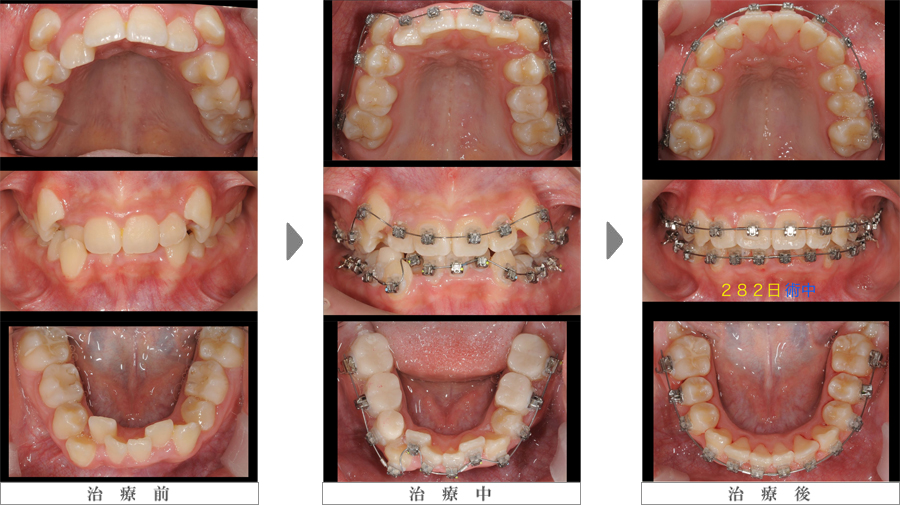

症 例

マルチブラケット装置

写真左列:上下叢生の患者様

写真中列:矯正装置装着直後

写真右列:治療開始後 約10ヶ月